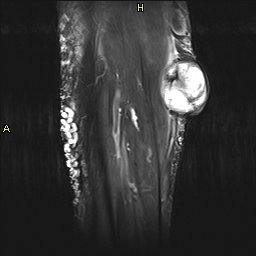

La radióloga con estos datos decide ampliar el estudio con RMN donde se observa que la lesión tiene aspecto heterogéneo con áreas hipo intensas sobre todo centrales con artefacto ferromagnético con secuencias en eco gradiente que puede sugerir la existencia de restos de hemosiderina y áreas hiperintensas sugerentes de necrosis como ves en la imagen 9.

La lesión impronta de forma importante al gemelo medial y parece infiltrar a la fascia del mismo.

Desde el punto de vista técnico y sin entrar en más detalles ya que este blog es de eco y el que escribe no da para más, te enseño cuatro cortes de RMN de la lesión estudiada posteriormente a la ecografía.

La imagen 6 te muestra un corte anatómico potenciado en T1 que nos va a mostrar relación anatómica de las estructuras. Cuando veas la imagen 7 y 8 te irás dando cuenta que la patología se muestra mucho más marcada ya que son corte axial y sagital y potenciado en un T2.

En el corte axial T2 puedes ver la gran cantidad de varices que superficialmente se observan en este corte, en formas circulares de distintos tamaños.

Puedes ver el comportamiento de la lesión en ambas potenciaciones y en al menos dos cortes ortogonales.